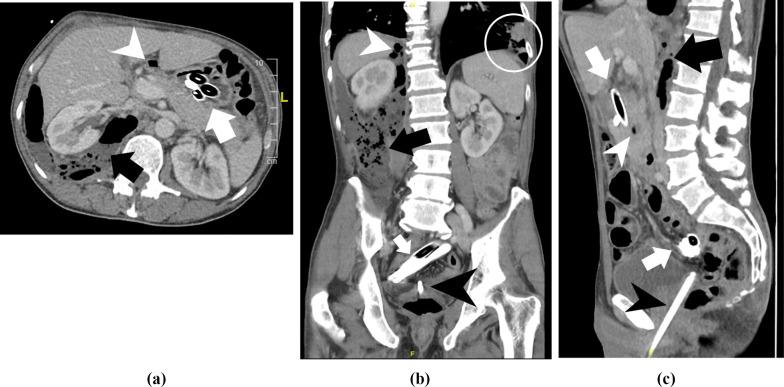

We present a case of a 62-year-old male who swallowed multiple thermometers with a length of up to 22 cm over a period of 40 years. Diagnostic imaging presented a retroperitoneal abscess due to a duodenal perforation of the longest thermometer as well as multiple other thermometers stuck in the small intestine. After all thermometers were removed and the abscess drained, the patient showed a clinical deterioration. In further operations we found a duodeno-sigmoid fistula and a gastro-thoracal fistula, which were not visible in the initial operations and imaging.

我们报告一例62岁男性病例,该患者在40年时间里吞食了多支长达22厘米的体温计。诊断性影像学检查显示,由于最长的体温计导致十二指肠穿孔,进而形成腹膜后脓肿,同时还有多支体温计卡在小肠内。在取出所有体温计并引流脓肿后,患者病情出现恶化。在后续手术中,我们发现了十二指肠-乙状结肠瘘和胃-胸瘘,这些在最初的手术和影像学检查中均未发现。